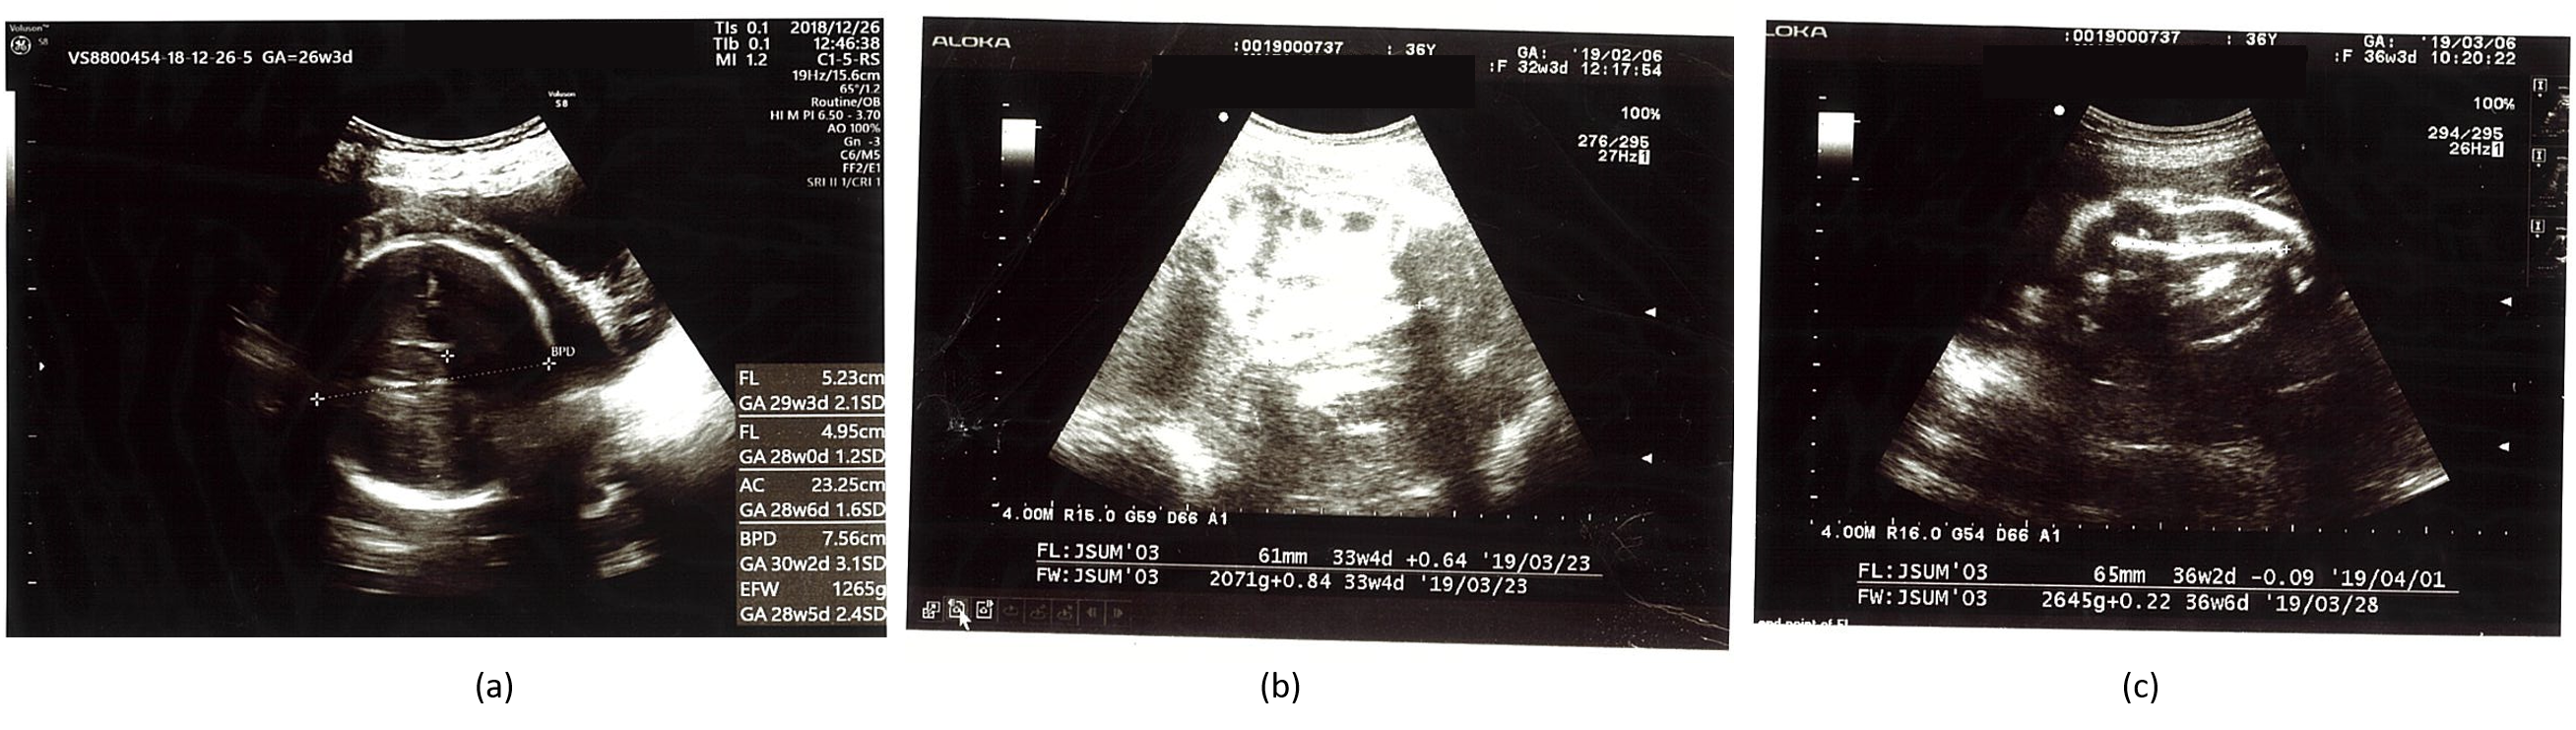

| Gestational Age | BPD (mm) | HC (mm) | AC (mm) | FL (mm) | EFBW (g) |

|---|---|---|---|---|---|

| 26w3d | 76 + 3.1 SD 97.5% | -- | 233 + 1.6 SD 95% | 52 + 2.1 SD 97% | 1265 + 2.4 SD 97% |

| 27w5d | 75 + 1.6 SD 90% | -- | 242 + 1.3 SD 90% | 56 + 2.3 SD 97% | 1421 + 2.0 SD 97% |

| 30w1d | 82 + 1.83 SD 90% | 301 ▲ 97% | 275 + 1.9 SD 95% | 60 + 1.9 SD 97% | 1947 + 2.4 SD 97% |

| 32w3d | 87 + 1.8 SD 90% | -- | 274 + 0.65 SD 50% | 61 + 0.64 SD 50% | 2071 + 0.84 SD 97% |

| 34w1d | 91▲ 50% | 339 ▲ 97% | 290 + 0.6 SD 10% | 67 + 1.5 SD 90% | 2480 + 1.2 SD 50% |

| 36w3d | 93 + 1.47 SD 50% | -- | 303 + 0.4 SD 10% | 65 − 0.09 SD 10% | 2645 + 0.22 SD 50% |

| 37w3d | 95 + 1.5 SD 50% | -- | 302 − 0.02 SD 10% | 73 + 1.75 SD 90% | 2886 + 0.44 SD 50% |